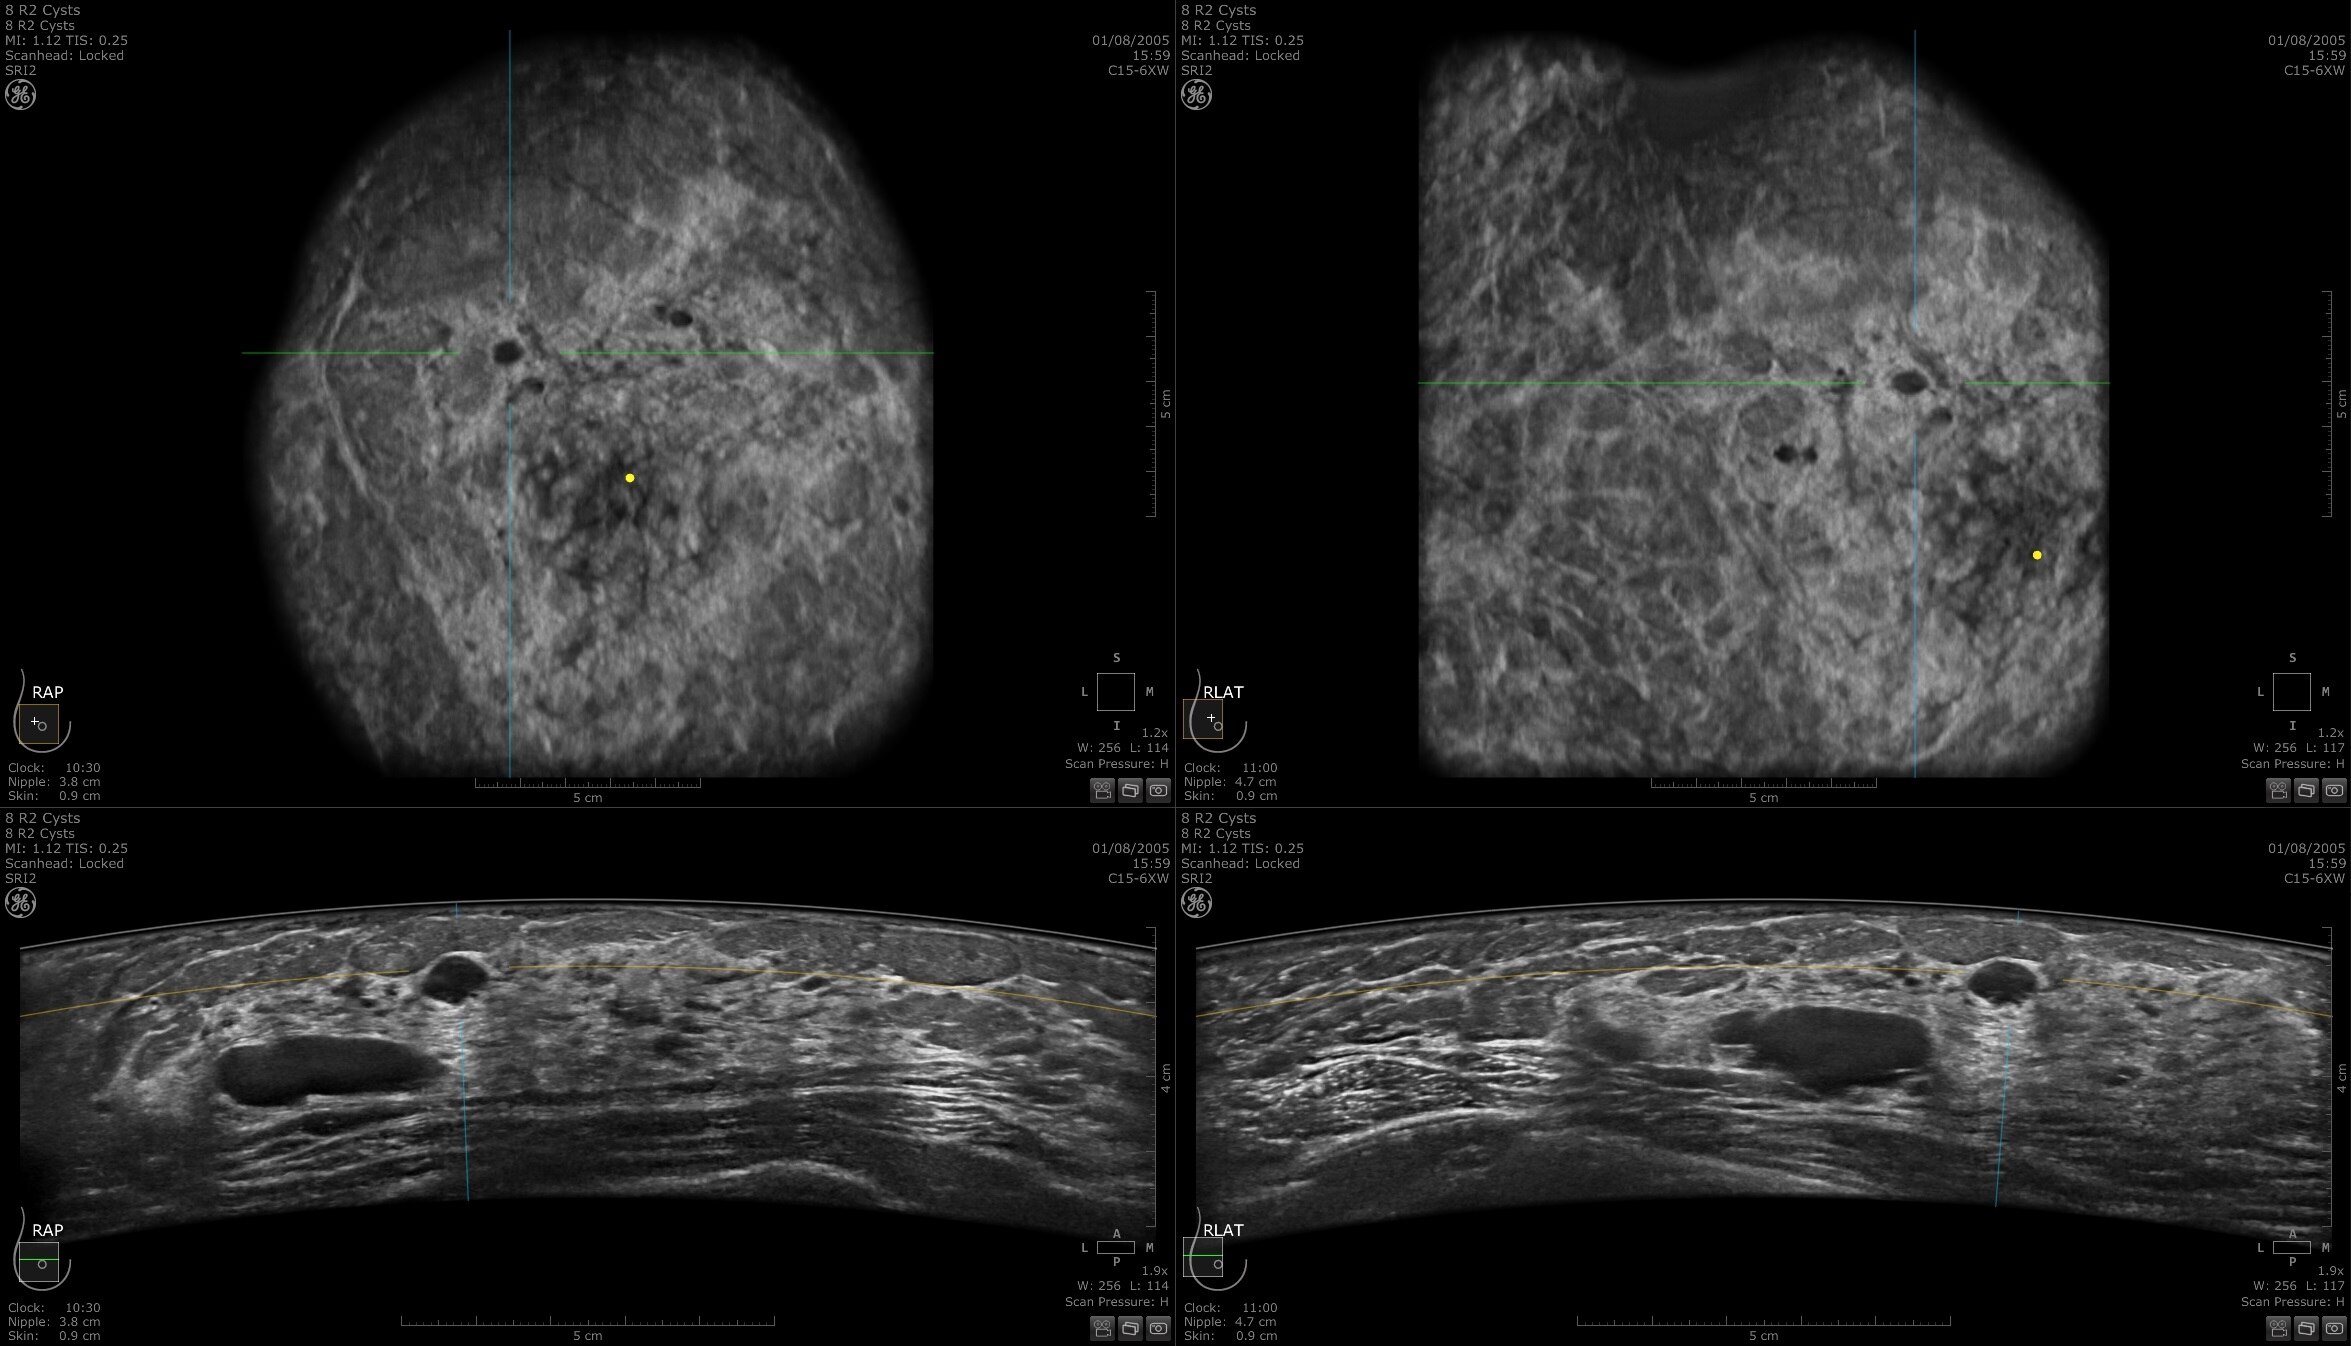

Invenia Abus Breast Imaging Ultrasound

Invenia ABUS 2.0, is the first FDA-approved ultrasound supplemental screening technology specifically designed for detecting cancer in dense breast tissue.

Invenia ABUS 2.0 transforms breast care from reactive to proactive, helping to detect breast cancers in dense tissue

Approximately 40% of women have dense breasts2, one of the strongest common risk factors for developing breast cancer3. Clinical evidence is growing about the effectiveness of ultrasound for finding small, node-negative, invasive cancers missed by mammography4. Invenia ABUS 2.0 supplemental imaging is designed for the screening environment, specifically for dense breast imaging.

Dense breast tissue and cancer appear white on a mammogram, potentially camouflaging small cancers. Invenia ABUS 2.0, is specifically designed to help clinicians find cancers that may be hidden on mammography1,2.

Invenia ABUS 2.0 uses the latest ultrasound innovations and AI based solutions to help improve precise diagnosis and elevate clinical confidence.